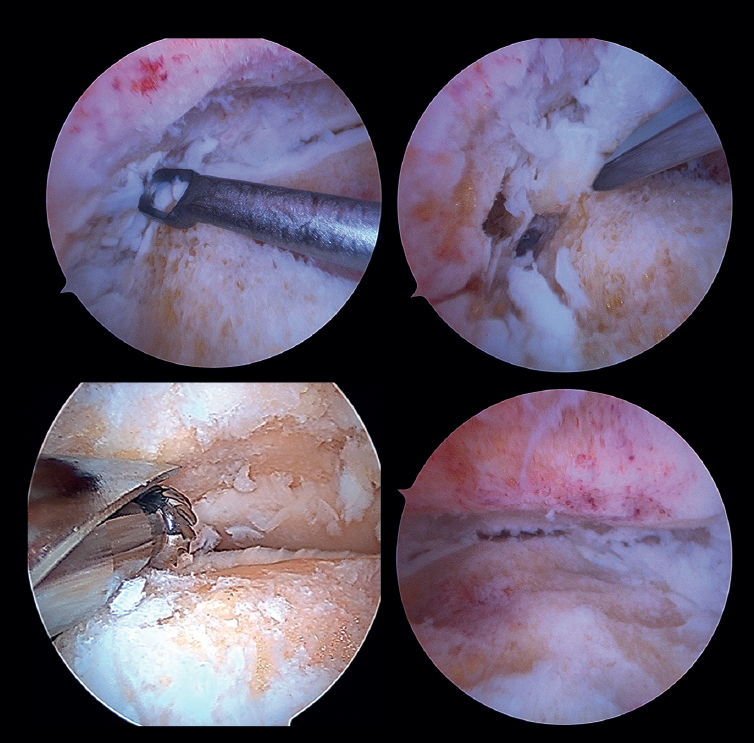

Preparation of the joint surfaces (Figure 4)

- In case of significant synovitis or arthrofibrosis, initial debridement is performed with a synoviotome allowing visualization of the joint.

- Large anterior osteophytes may be present, and their initial resection may require the use of a burr, curette or osteotome, taking care not to damage the anterior neurovascular structures. Resecting them from the start sometimes improves dorsiflexion of the talus and affords a better neutral position in the sagittal plane, as well as better visualization of the operating field.

It is useful to exchange viewing and working portals to access the full extent of the cartilage surfaces and to check complete resection.

The vaporizer is useful in cases of severe fibrotic impingement, which is characteristic of post-traumatic or second surgery scenarios, but again we should work as close to bone or joint space as possible, in order to avoid anterior tissue injury. - It is usually not necessary to use a distraction device to open the joint, since the joint space will progressively grow as the remaining joint cartilage is resected.

- Surgical curettage is performed, with chondral delamination and excision of the cartilage tissue until a viable cancellous bone bed is obtained. This can be done with or without motorized burr support, depending on each case.

- For preparation of the recesses, medial and lateral accessory portals can be used for drilling or curettage of both the medial aspect of the distal fibula and the lateral aspect of the medial malleolus.

- In cases of advanced syndesmotic lesions with marked widening, syndesmotic fusion is recommended, especially in cases of valgus arthropathy. The tibiofibular joint surface is typically prepared with one of the chosen shaver terminals.

- All residues are removed with specific instruments. Perforations can be added to obtain bleeding areas in the subchondral bone.

- Soft tissue release is performed, if necessary. This fundamentally applies to the deltoid ligament when there is a varus component in the joint disorder.

- In patients with major defects or poor bone stock, structural auto- or allografts are used on a case-by-case basis. We may require widening of the portals for their placement or mini-arthrotomies.